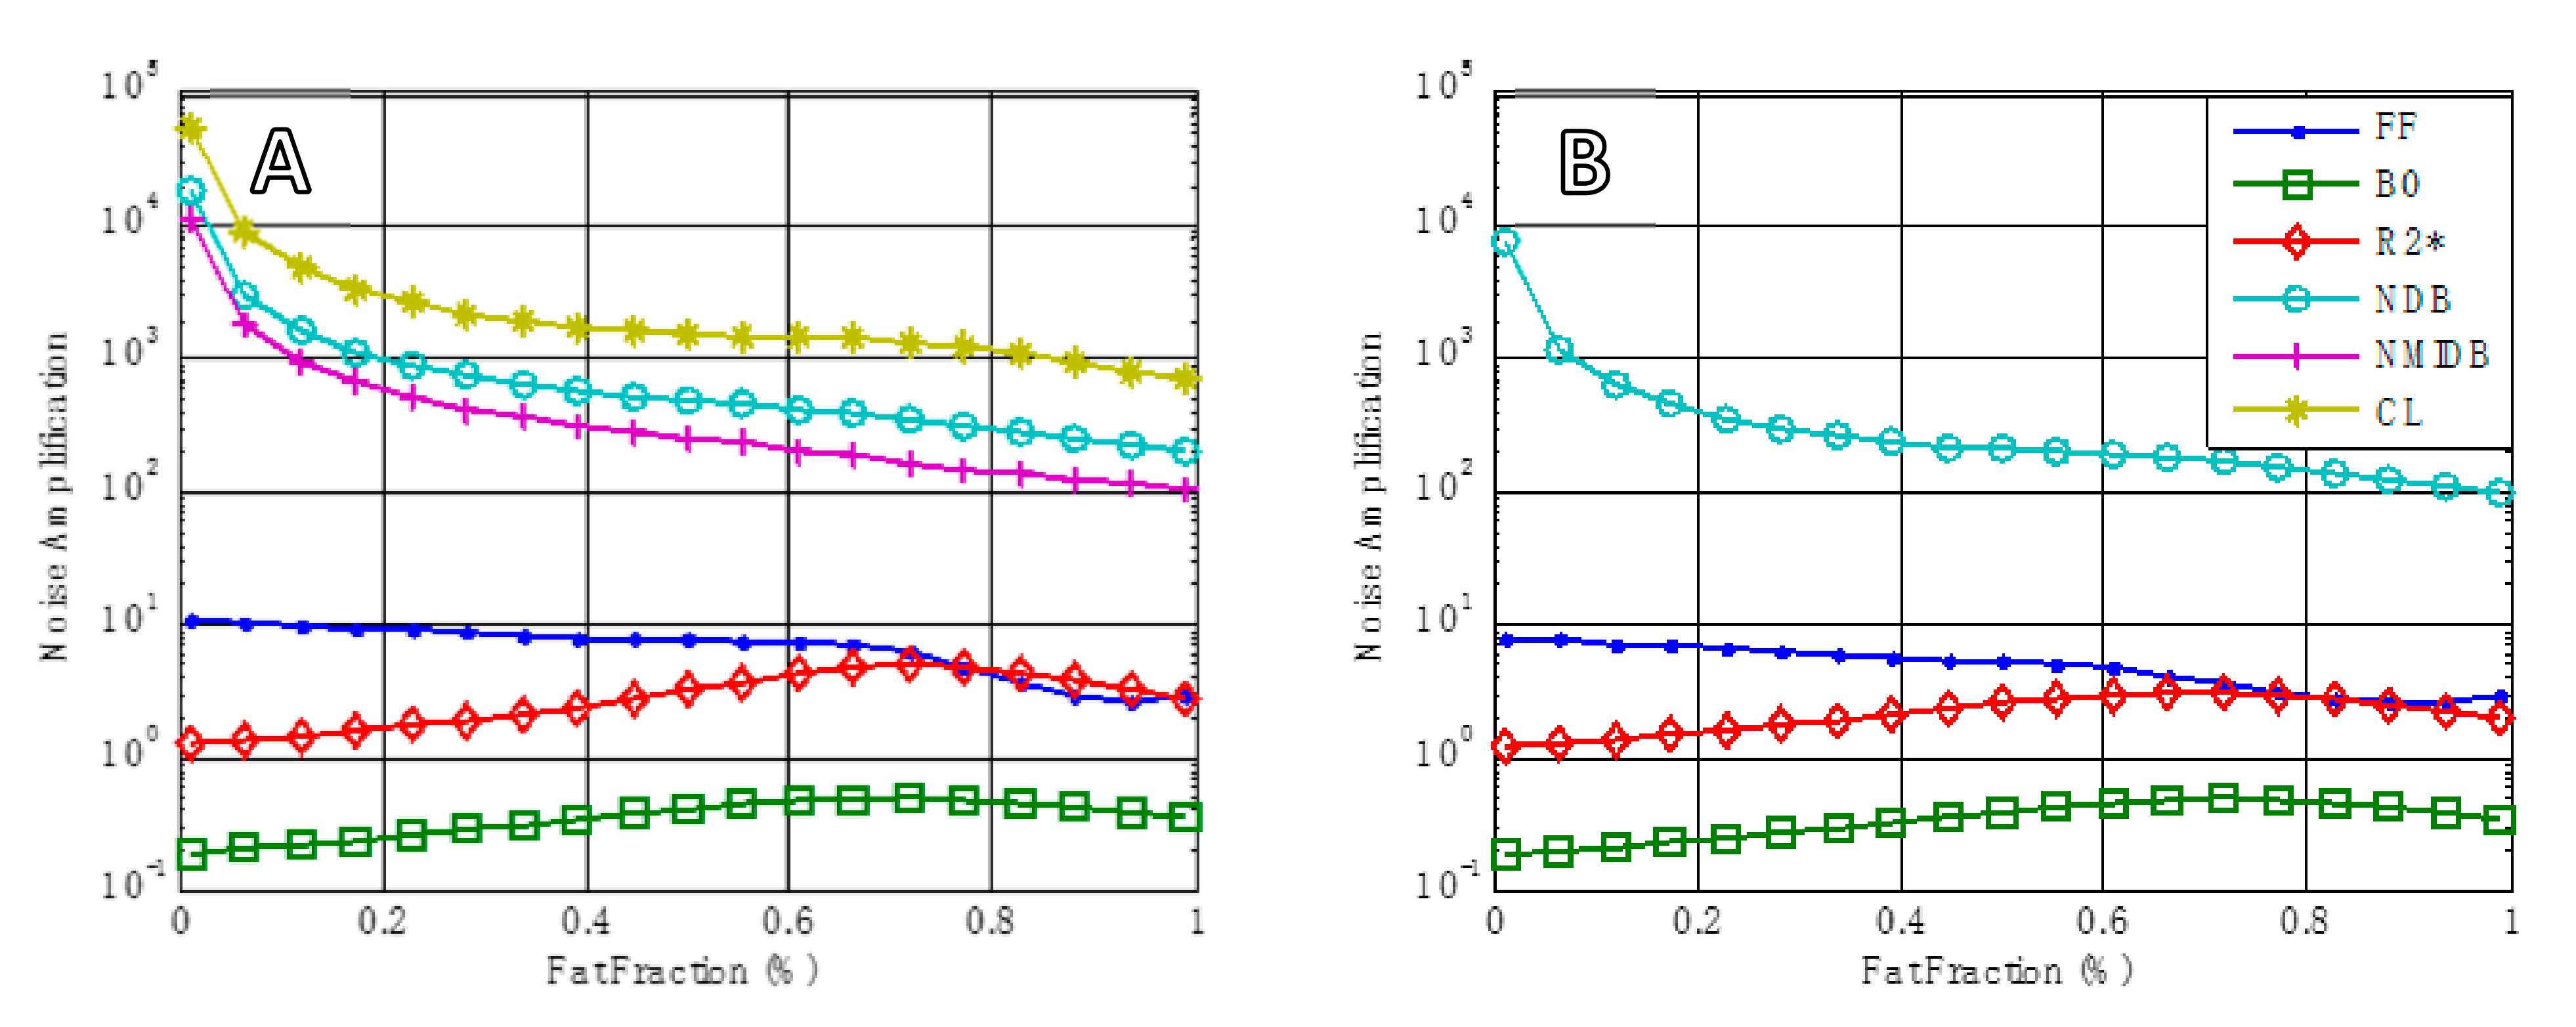

- The following correlations were performed:

- Spectroscopy: NDB in subcutaneous versus visceral tissue.

- Imaging: global NDB versus subcutaneous.

- Spectroscopy NDB versus imaging NDB (subcutaneous).

- Spectroscopy NDB versus NAS.